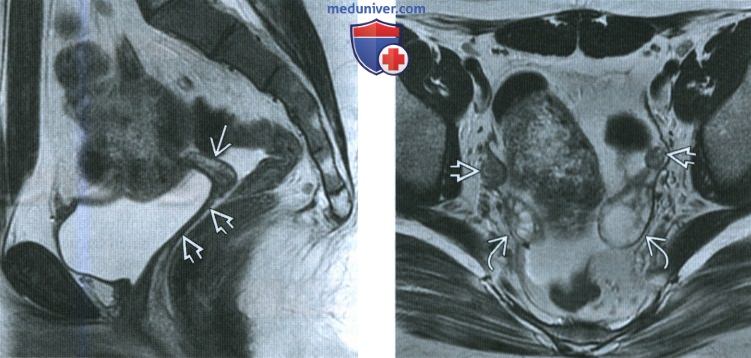

Медицинская визуализация: Признак Кюстнера-Чукалова